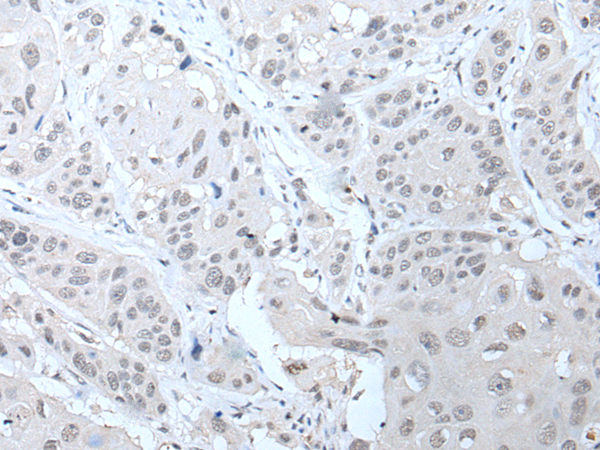

The image is immunohistochemistry of paraffin-embedded Human thyroid cancer tissue using P12779(PPP1R42 Antibody) at dilution 1/20. (Original magnification: ×200) |

The image is immunohistochemistry of paraffin-embedded Human liver cancer tissue using P12779(PPP1R42 Antibody) at dilution 1/20. (Original magnification: ×200) |